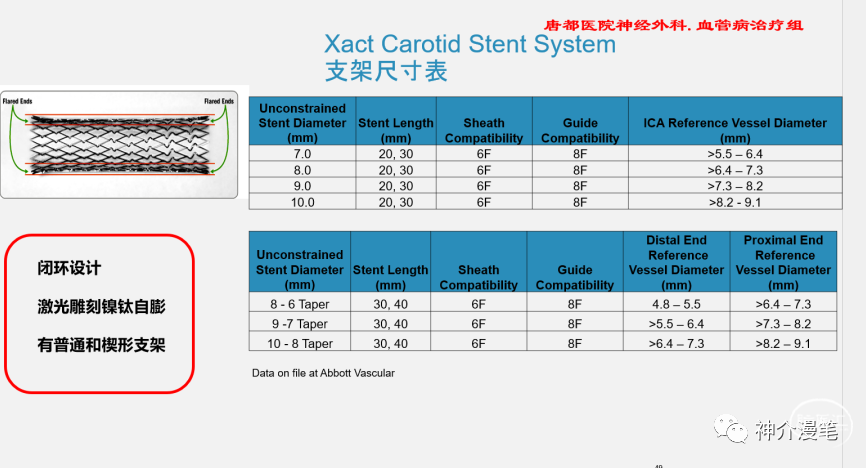

雅培系列支架

雅培上面两款支架一个开环,一个闭环,应用的场景,使用原则和上诉所说的支架大体差不多,大家可以再看一下他们的具体型号和尺寸。酌情使用,比较有意思的是这两款支架的释放都是“半自动化的”,支架到位后通过旋转释放手柄或回拉把手即可完成。不需要前面几款支架的推扒技术,所以一旦支架到位良好,释放极度简单,几乎就是傻瓜式释放,特别适合新手小白使用。